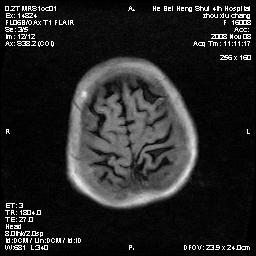

标题: MRI1883:女67岁,半年前曾患脑梗塞,治疗后好转,近3各月精 [打印本页]

标题: MRI1883:女67岁,半年前曾患脑梗塞,治疗后好转,近3各月精

女67岁,半年前曾患脑梗塞,治疗后好转,近3各月精神恍惚。